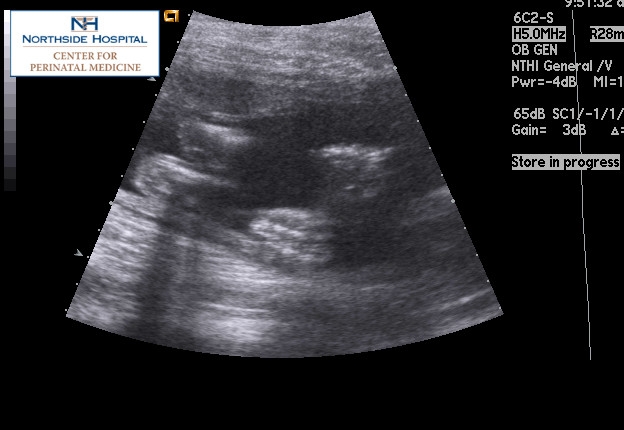

DH and I just got in from my perinatal doc. Michael is weighing in at 1 lb 14 ozs (I'm kinda freaking out, as that seems big), and looks good. Here's a pic of him pushing his hands and feet against me, and another of just his feet.

I also had another U/S cos they couldn't get a good measurement of his spine the last time, so that was first. I had my mom with since DH couldn't make it, and I know she enjoyed seeing her grandbaby on the screen. However, he wasn't cooperating and they couldn't get another measurement. So, I get to have another U/S done 9/20. This is the same day as my already scheduled Glucose Test and checkup... so I am basically spending my day at the hospital (11:45 U/S, 1:10 Glucose, 1:30 appt).

My OB said that there wasn't any big concerns with it, just that they couldn't get what they wanted. I guess I don't mind seeing him again, but am not looking forward to paying it 3X.